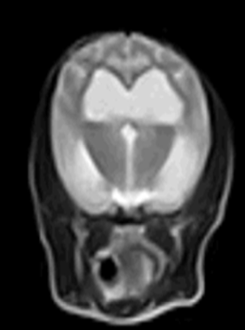

| T1 | T2 |

![]() | ![]() |

- ์์ชฝ ๋ผ๊ฐ ๋น์ด ์์ (๊ตฌ๋ฉ, ์ฒ๊ณต)

- ๋์ฒ์์ก์ด ์ ๋น ์ ธ๋๊ฐ์ง ๋ชปํด ์ธก๋์ค์ด ์์ชฝ ๋ชจ๋ ํ์ฅ๋จ.

- ๋์ฒ์์ก์ด cerebral cortex๋ฅผ ๋๋ฅด๋ฉด์ ์์์ง.

โ ICP ๋์์ด ์์น, seizure ๋ฐ์

โ Severe Symmetrically ventriculomegaly (์ฆ, Hydrocephalus)

DAMNIT-V ์ค A์ ํด๋น. ์์น ์ ๋จ.